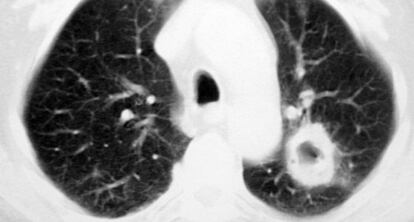

Un estudio publicado este lunes por el Journal of American Medical Association (JAMA) Internal Medicine añade argumentos (en contra) a este debate. El trabajo alerta del elevado porcentaje de falsos positivos: un 18% a partir de la revisión efectuada en 53.452 estudios con tomografía computerizada de baja dosis.

En esta población, en un 20% de los casos se detectan nódulos pequeños (de 5 a 10 milímetros) que suelen acabar en el quirófano. Pero de ellos, en torno a otro 20% -como refleja el estudio presentado este lunes- serían falsos positivos, como apunta Massuti. Y aquí está el problema, ya que es una cifra “excesiva”, comenta el también jefe de servicio de oncología del Hospital General de Alicante.